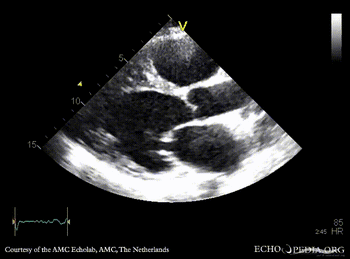

A4CH A4CH with Color Doppler: severe mitral valve regurgitation